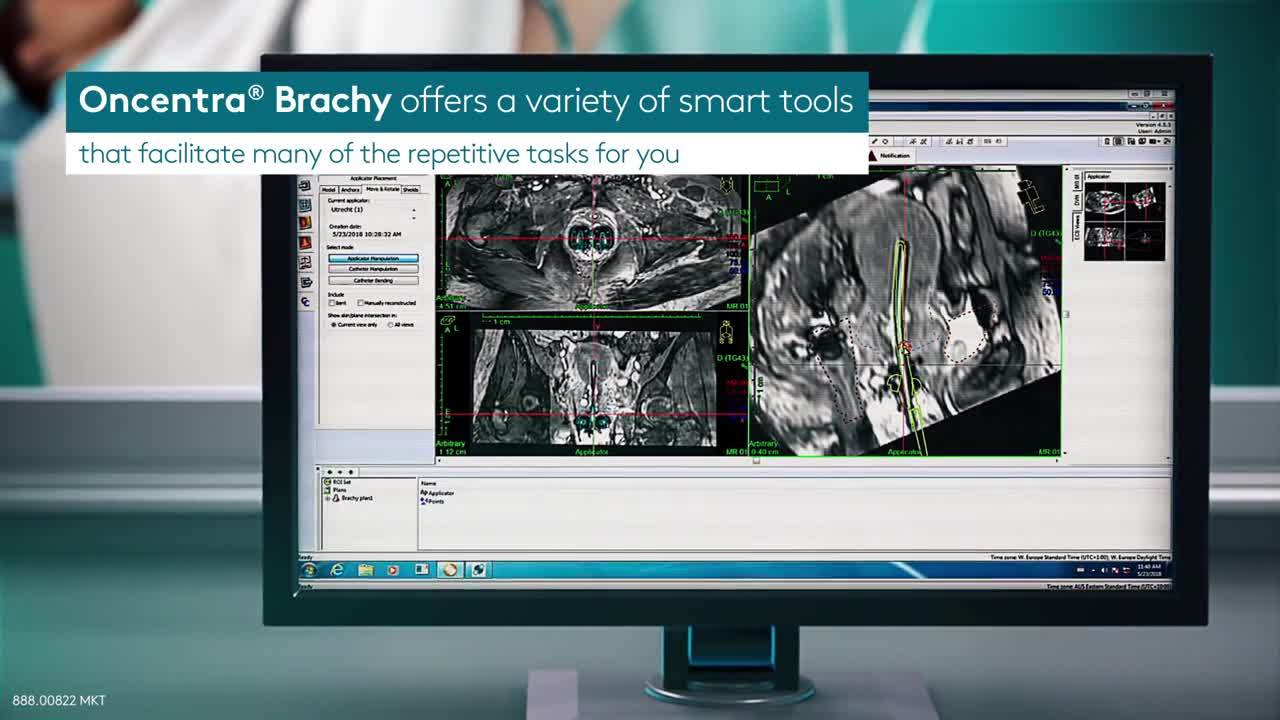

优化剂量分布的设计工作非常耗时。最新版Oncentra Brachy提供了一系列实用工具,可帮助简化许多重复性任务,例如勾画和重建。Oncentra Brachy让您能够节省时间,集中精力来确定最佳的剂量分布。

Oncentra Brachy还有助于提高治疗计划的准确性,让您能够轻松导航至任意层面,获取每个感兴趣区域的最相关信息。其中,针对重复性任务的模板解决方案-例如,新推出的植入物建模工具,以及受欢迎的施源器建模功能,有助于缩短植入物重建时间。DVH预设和ROI目录管理器可帮助提高妇科近距离治疗的准确性和再现性。强大的逆向计划优化功能则可自动执行基于体积的计划,确保迅速高效地完成计划。